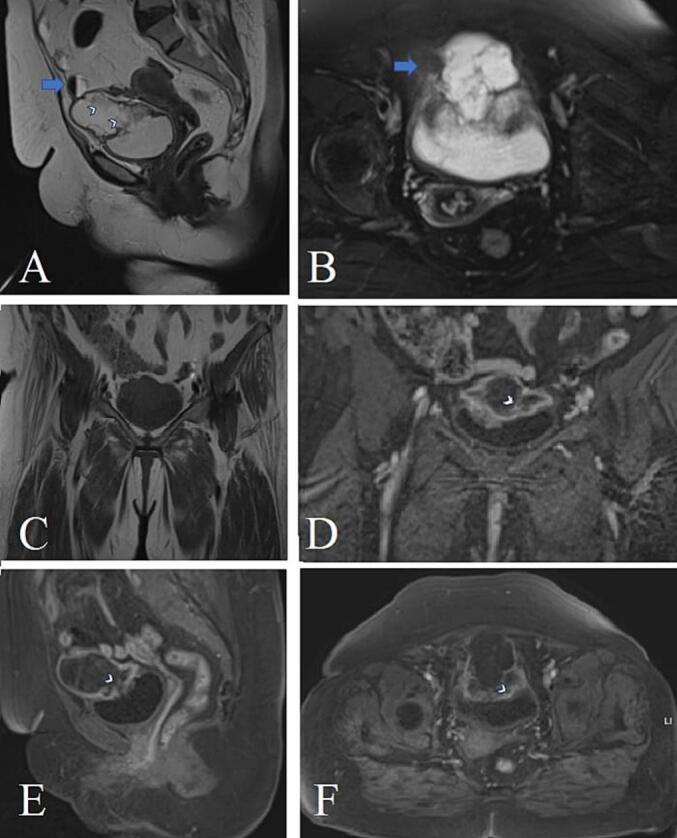

We present the case of a 58-year-old female who exhibited painless hematuria, leading to further investigation. The definitive diagnosis of invasive mucinous urachal adenocarcinoma was established through cystoscopy and transurethral resection of bladder tumor (TURBT). Surgical intervention was undertaken to manage the condition.

我们报告一例58岁女性,表现为无痛性血尿,遂进一步检查。通过膀胱镜检查和经尿道膀胱肿瘤切除术(TURBT)确诊为侵袭性黏液性脐尿管腺癌。采取了手术干预来治疗该疾病。